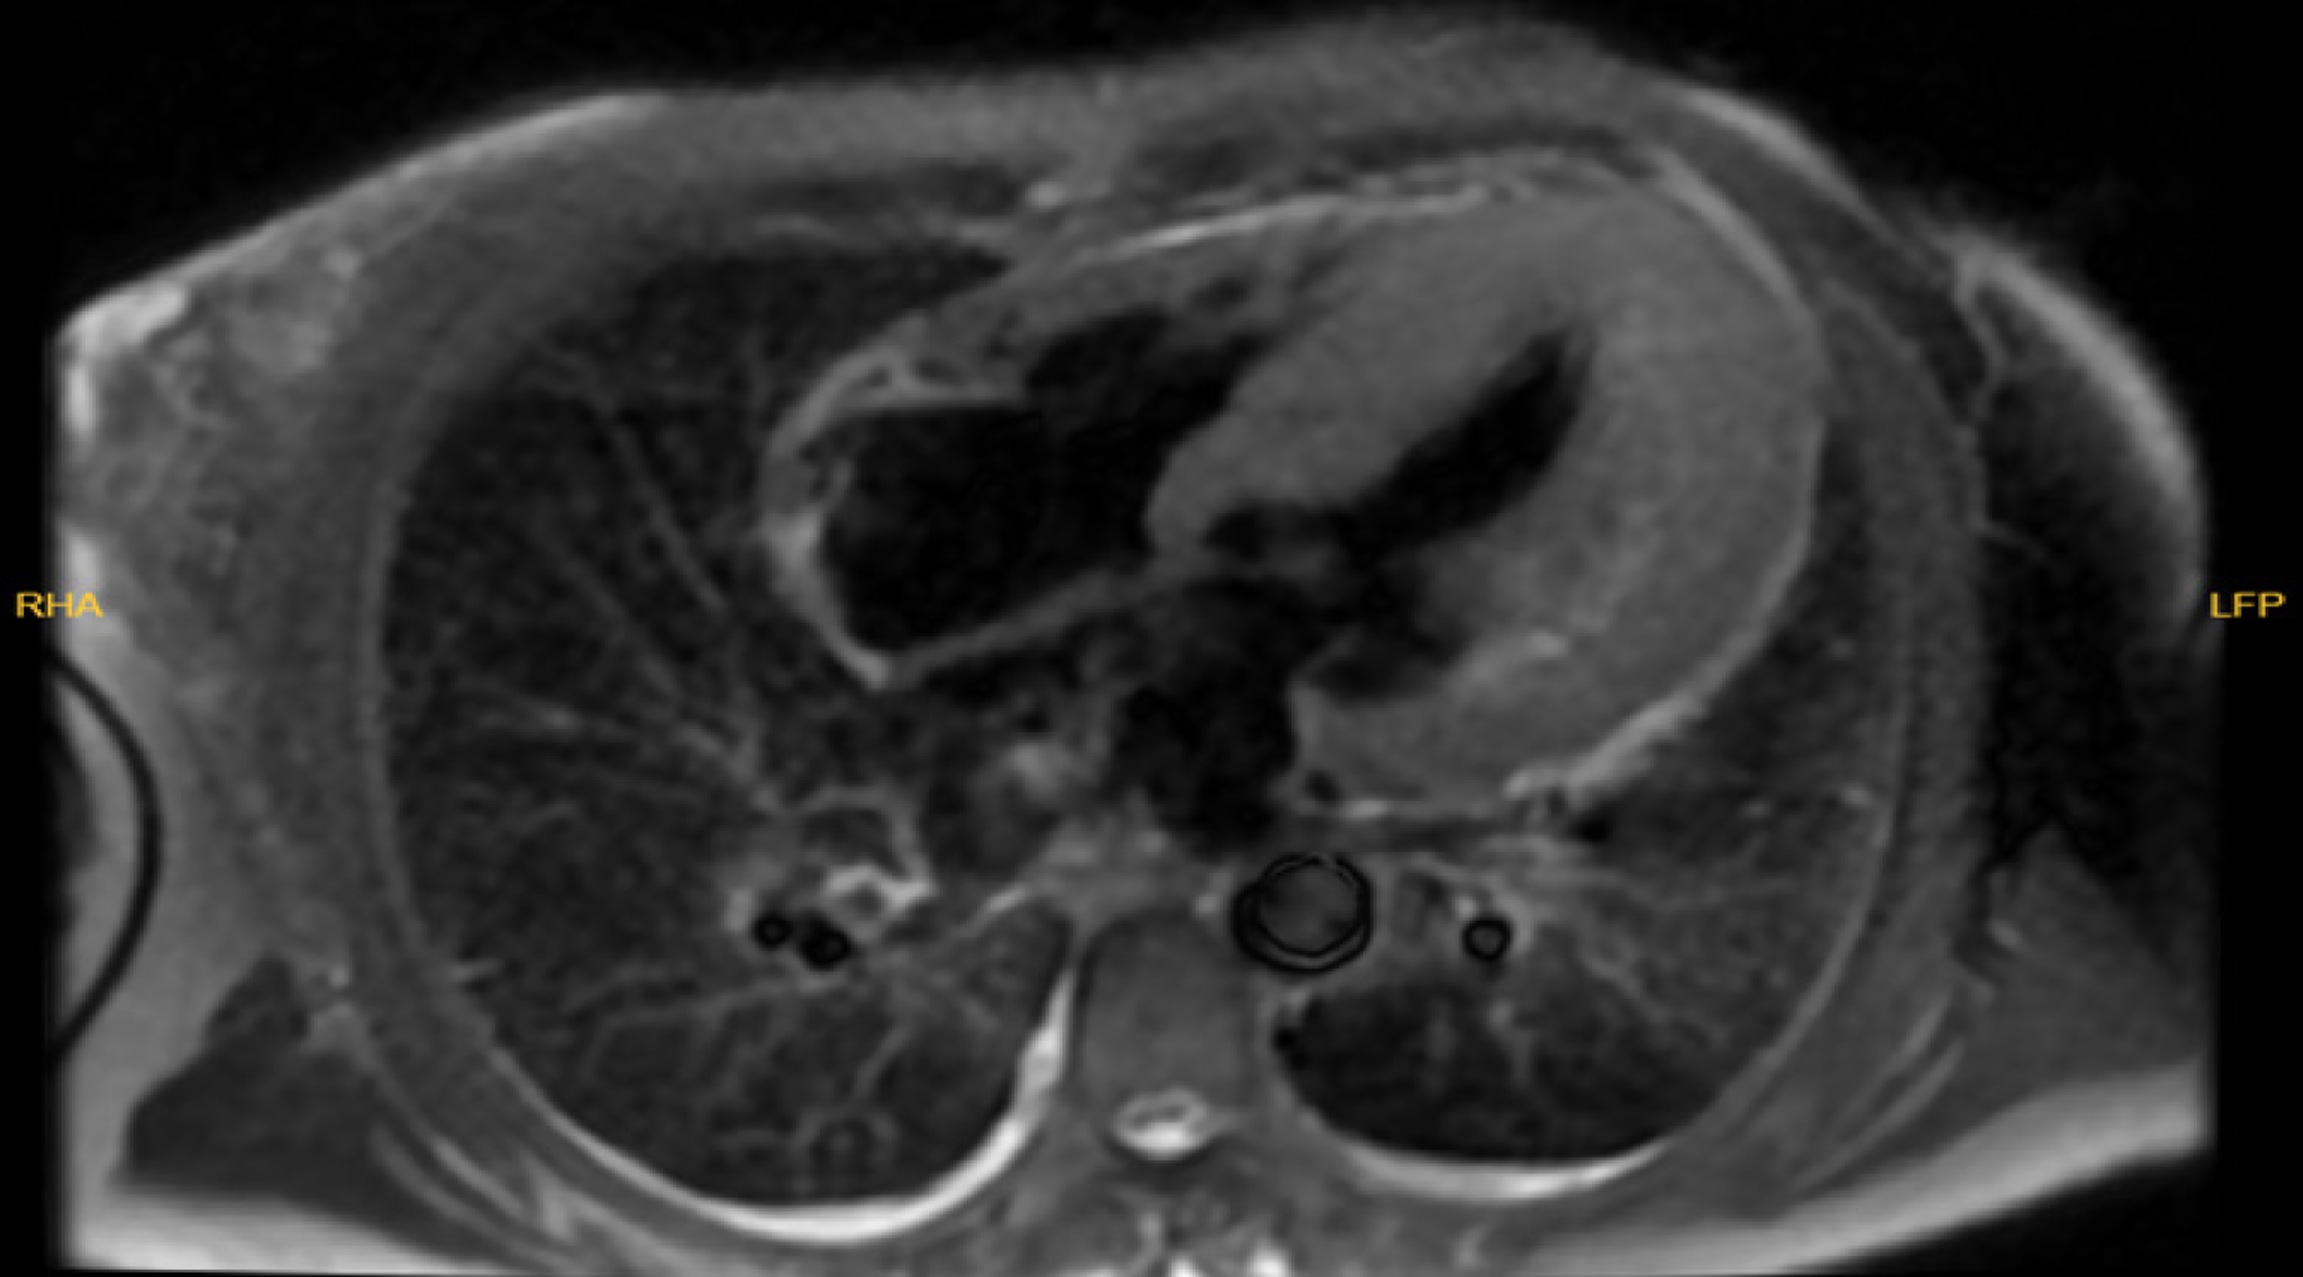

Figure 2 Cardiac magnetic resonance demonstrating diffuse asymmetric left ventricular hypertrophy with mid-wall late gadolinium en hancement consistent with non-ischemic fibrosis.